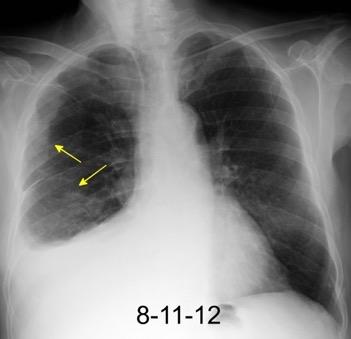

100. TUMOR FANTASMA

En relación con trasudados tabicados. Insuficiencia cardiaca

Derrame pleural “encapsulado”

“Tumor fantasma”

Asociado a fallo cardiaco. ( “Pleuritis adhesiva”). Buch KP. Chest. 2000